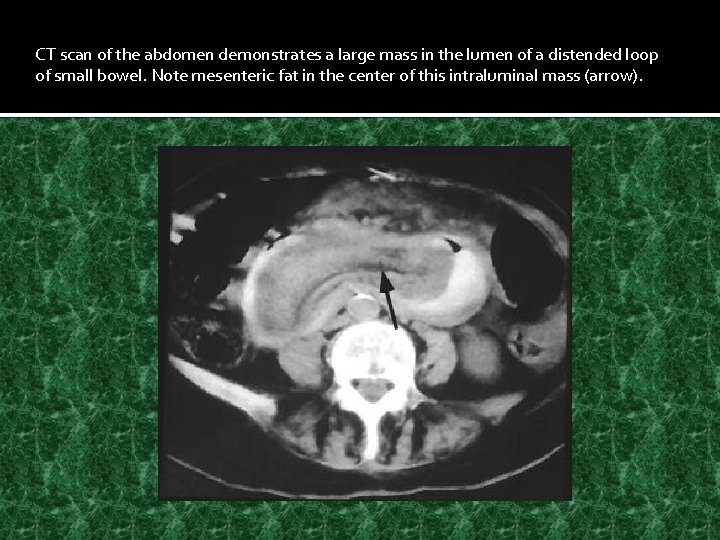

CT scan of the abdomen demonstrates a large mass in the lumen of a distended loop of small bowel. Note mesenteric fat in the center of this intraluminal mass (arrow).